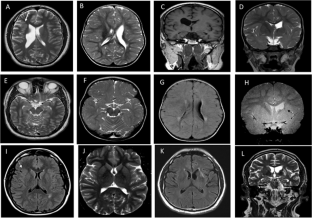

Genetic alterations in COL4A2 are less common than those of COL4A1 and their fetal phenotype has not been described to date. We describe a three-generation family with an intragenic deletion in COL4A2 associated with a prenatal diagnosis of recurrent fetal intracerebral hemorrhage (ICH), and a myriad of cerebrovascular manifestations. Exome sequencing, co-segregation analysis, and imaging studies were conducted on eight family members including two fetuses with antenatal ICH. Histopathological evaluation was performed on the terminated fetuses. An intragenic heterozygous pathogenic in-frame deletion; COL4A2, c.4151_4168del, (p.Thr1384_Gly1389del) was identified in both fetuses, their father with hemiplegic cerebral palsy (CP), as well as other family members. Postmortem histopathological examination identified microscopic foci of heterotopias and polymicrogyria. The variant segregated in affected individuals demonstrating varying degrees of penetrance and a wide phenotypic spectrum including periventricular venous hemorrhagic infarction causing hemiplegic CP, polymicrogyria, leukoencephalopathy, and lacunar stroke. We present radiographic, pathological, and genetic evidence of prenatal ICH and show, for what we believe to be the first time, a human pathological proof of polymicrogyria and heterotopias in association with a COL4A2 disease-causing variant, while illustrating the variable phenotype and partial penetrance of this disease. We highlight the importance of genetic analysis in fetal ICH and hemiplegic CP.